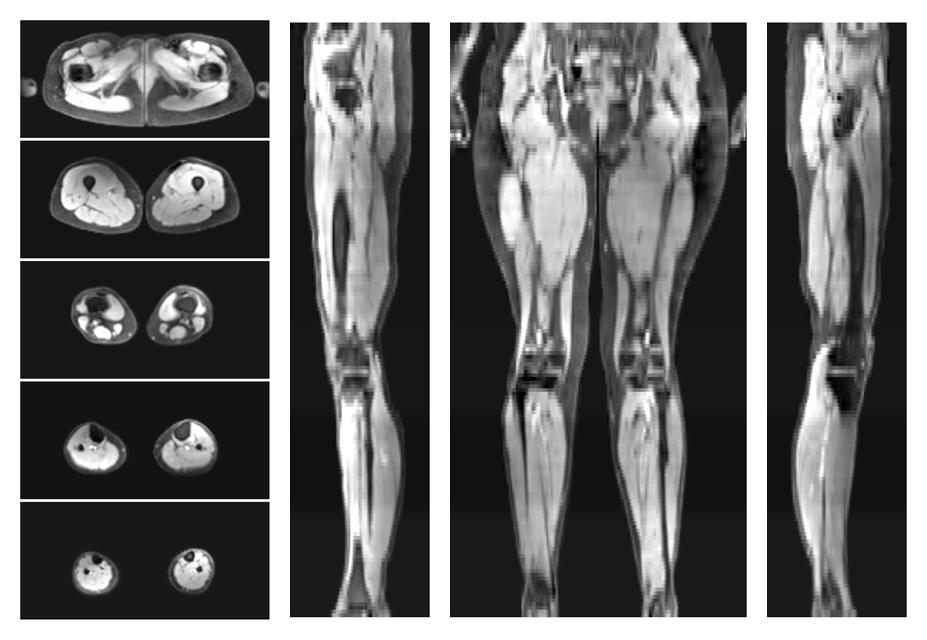

• Water only signal

The water part of the acquired multi-echo spin echo data.